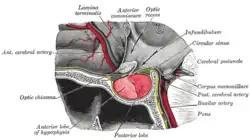

A major organ of the endocrine system, the anterior pituitary (also called the adenohypophysis or pars anterior) is the glandular, anterior lobe that together with the posterior lobe (posterior pituitary, or the neurohypophysis) makes up the pituitary gland (hypophysis) which, in humans, is located at the base of the brain, protruding off the bottom of the hypothalamus.

Structure

The pituitary gland sits in a protective bony enclosure called the sella turcica (Turkish chair/saddle). It is composed of three lobes: the anterior, intermediate, and posterior lobes. In many animals, these lobes are distinct. However, in humans, the intermediate lobe is but a few cell layers thick and indistinct; as a result, it is often considered part of the anterior pituitary. In all animals, the fleshy, glandular anterior pituitary is distinct from the neural composition of the posterior pituitary.

Additional images

The anterior pituitary is the anterior, glandular lobe of the pituitary gland.

The anterior pituitary is the anterior, glandular lobe of the pituitary gland.